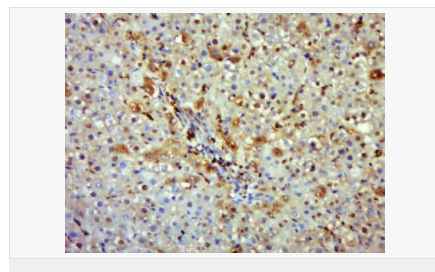

產品應用WB=1:500-2000 IHC-P=1:100-500 IHC-F=1:100-500 Flow-Cyt=1μg/Test ICC=1:100-500 IF=1:100-500 (石蠟切片需做抗原修復)

image.png